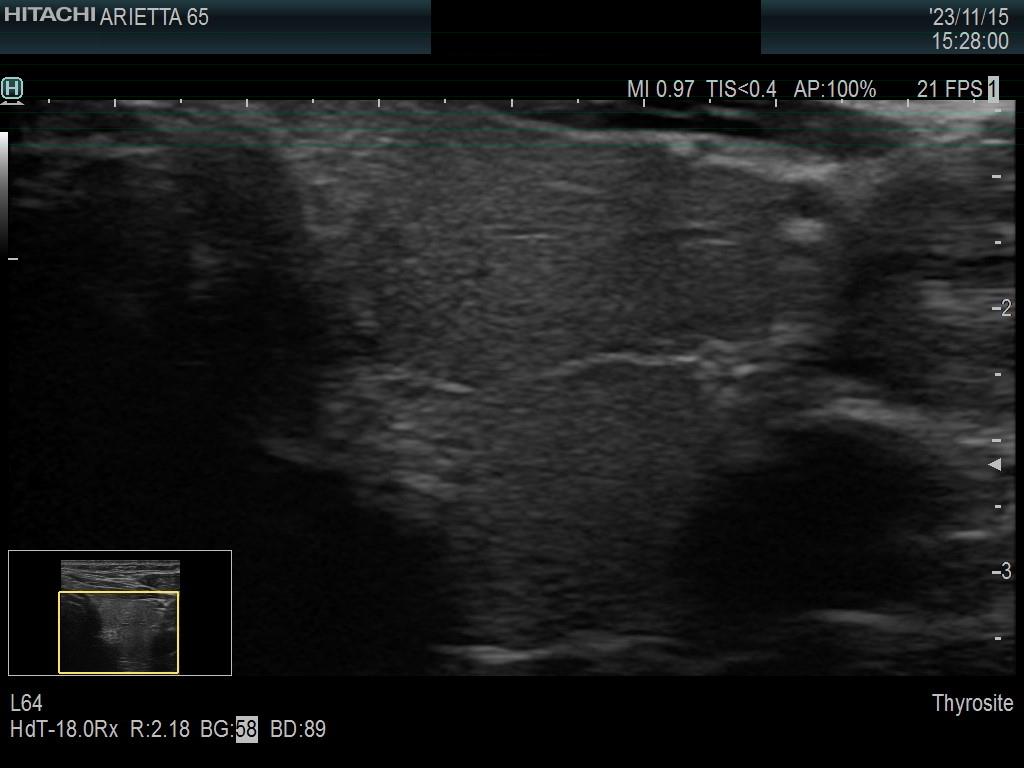

Left lobe, transverse scan - enlarged view. The presence of the connective tissue makes the dorsal part deceptively nodular.